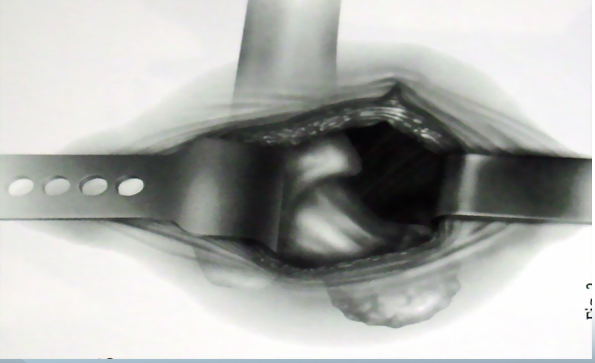

沿阔筋膜纤维方向切开扩筋膜大粗隆顶点臀中肌前1/3处沿纤维方向分离臀中肌

横形切开臀小肌2cm

沿大粗隆前缘切开臀中肌腱和臀小肌

切除关节囊髋关节内收、屈曲、外旋位脱位

准备髋臼

准备股骨髓腔

缝合切开之臀小肌和臀中肌